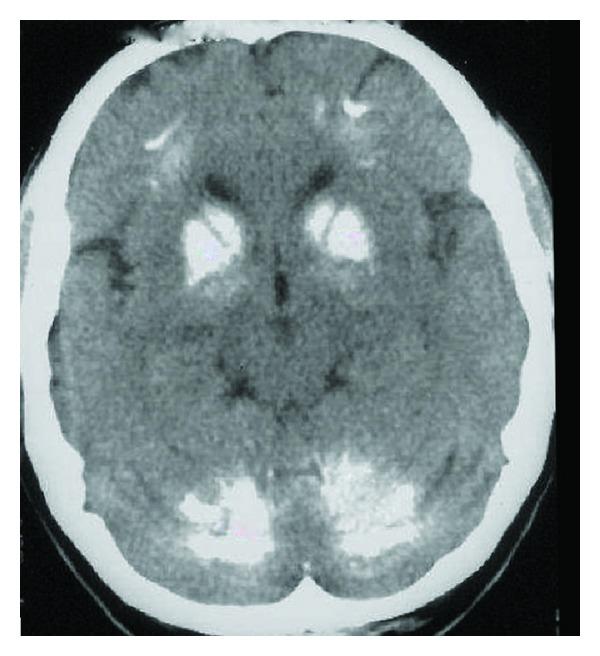

Fahr's disease (FD) is characterized by sporadic or familiar idiopathic calcification of the basal ganglia, dentate nuclei of the cerebellum, and centrum semiovale, mainly presenting with movement disorder, dementia, and behavioral abnormalities. We described a rare case of Fahr's disease presenting at onset only with behavioral and neuropsychological alterations, whose diagnosis was supposed only after a brain CT, which showed extensive bilateral calcifications in the dentate nuclei of the cerebellum and basal ganglia. Since the onset of Fahr's disease may be a dysexecutive syndrome with behavioral abnormalities, the clinical and radiological features are really important to do the appropriate diagnosis.

Fahr 病(FD)的特征是基底节、小脑齿状核和大脑半卵圆中心的散发性或家族性特发性钙化,主要表现为运动障碍、痴呆和行为异常。我们描述了一例 Fahr 病的罕见病例,其首发症状仅为行为和神经心理学改变,仅在脑 CT 显示小脑齿状核和基底节广泛双侧钙化后才作出诊断。由于 Fahr 病的发病可能是一种伴有行为异常的执行功能障碍综合征,因此临床和影像学特征对于做出适当的诊断非常重要。